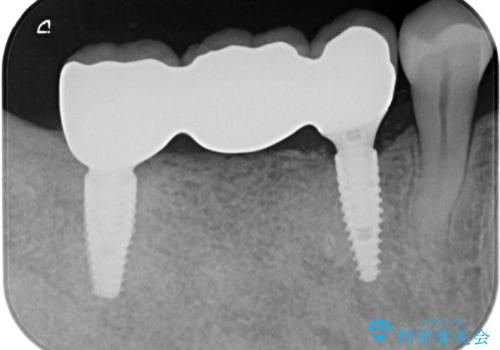

失った奥歯をインプラントで機能回復

- 110万円(インプラント×2・チタンカスタムアバットメント×2・ジルコニアクラウン×3・仮歯×3)費用は治療当時の料金となります

審美性が向上したとともに、またしっかりと噛めるようになったことで食事も楽しめるようになりました。